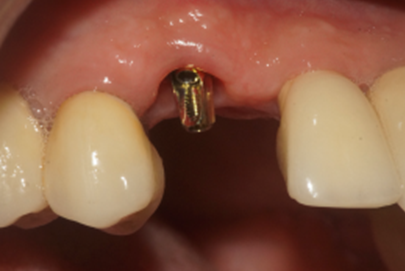

Após 90 dias da instalação do implante, o cicatrizador foi removido e fazendo uso do Kit de Seleção de Componentes da mesma empresa, foi selecionado um pilar Ideale angulado de 3.3 X 4.0 X 1.5 de 17°. Essas mediadas se referem ao diâmetro, altura protética, altura do transmucoso e ao ângulo do pilar, respectivamente (Figuras 9, 10 e 11).

Figura 9 – Cicatrizador removido após 90 dias

Figura 10 – Pilar angulado sendo selecionado

Figura 11 – Verificando a emergência do parafuso

Figura 12 – Pilar Ideale de 3.3 X 4.0 X 1.5 de 17° instalado